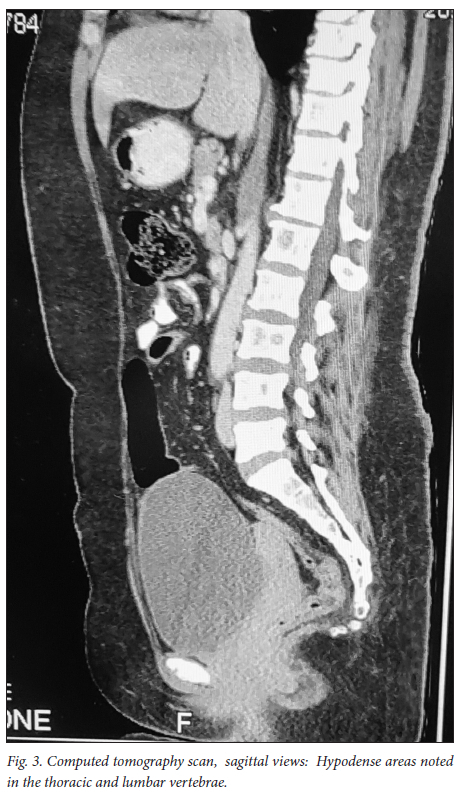

A 39-year-old obese woman had had a lump in the right breast for 18 months. She had gone to her local hospital when she noticed the lesion. A core biopsy was done and she was referred to the breast oncology clinic at Mankweng Hospital in Polokwane, Limpopo Province, South Africa, for further assessment and management. She had previously been healthy, with no known comorbidities and no family history of malignancy. On enquiry about her gynaecological history, she stated that her menarche had been at age 12, and she was still having normal periods and on contraception. She had a 15-year-old child, born when she was 24. After the birth of this child she had two more pregnancies, both resulting in unexplained stillbirths at term. She had no history of pregnancy-induced hypertension or any medical conditions diagnosed during pregnancy. After her discovery of the breast lump she was diagnosed with young-onset hypertension. There were no associated weight changes, and she was HIV negative. On examination she had a scar on the right upper quadrant, no palpable axillary lymph nodes, an elevated blood pressure (150/93 mmHg, pulse rate 88 bpm) and a high body mass index (37.7 kg/m2). The rest of the vital signs and the findings on systemic examination were unremarkable. On examination of the breast, the tumour was clinically staged as T3N0M0, making it stage IIB. Histological evaluation showed nests of cells infiltrating extensively throughout the tissue. The cells were hormone receptor (oestrogen and progesterone) positive, the HER2 score was 3+ and the Ki-67 proliferation index was 50 - 60%. Synaptophysin (SYP) and chromogranin (CGA) cytoplasmic staining was positive within the tumour cells, features in keeping with grade 3 invasive carcinoma showing neuroendocrine differentiation. A mammogram (Fig. 1) revealed poorly marginated density with a speculated mass noted on the upper inner quadrant at 1 o'clock on the middle portion of the right breast. The mass expended anteriorly to the retro-areolar space causing minimal traction of the peri-areolar skin and nipple. There were associated architectural distortions and trabecular thickening. The retromammary space was grossly normal bilaterally. There was no thickening of overlying skin, and no dilated ducts bilaterally. Regional benign calcifications were noted in the left breast. No axillary lymph nodes were visualised bilaterally. For further evaluation, a computed tomography (CT) scan (Figs 2, 3 and 4) was done and revealed multiple enlarged lymph nodes in the right axillary region. The right breast was ill defined with trabecular thickening and nipple retraction. The breast mass did not extend into the retromammary space, and the pectoralis muscle was grossly normal. Hypodense areas were noted in the thoracic and lumbar vertebrae, with involvement of the posterior elements. The right scapular blade and spine also had multiple hypodense areas. The lung parenchyma, the visualised liver, the stomach and the rest of the visualised bowel and the kidneys were grossly normal. With this evidence, the patient was diagnosed as having primary NEBC, with features suggestive of metastasis to the bones. A bone scan revealed widespread metastases in the skull and throughout the spine, pelvic bone, proximal femur and sternum. In view of this finding, the patient was re-assessed as having clinical stage IV disease. The management approach changed to focus on palliative care. There was no surgical intervention, and the patient was referred to the medical oncology clinic for further management, to come back if the need for surgical palliation arose.

Primary NEBCs are rare and the diagnosis therefore depends on excluding metastasis from other sites, because the two entities require different management approaches.[9] Diagnostic tools include the use of tumour markers such as CGA and SYP immune reactivity, which is significantly associated with a neuroendocrine neoplasm.[1,10] Importantly, elevated CGA levels are also associated with hypertension, obesity and heart failure,[11] among other conditions. On breast imaging with mammography and/or ultrasound, secondary NEBCs are oval in shape, with circumscribed or microlobulated margins.[12] Triple assessment is mandatory; however, histopathological assessment and immunohistochemistry staining are the mainstay of diagnosis. [1,13,14] Clinically, the presentation of NEBCs cannot be distinguished from other types of breast cancer. It has also been postulated that, unlike other breast cancers, NEBCs can present with clinical features related to hormonal secretion because of ectopic production of adrenocorticotrophic hormone, norepinephrine or calcitonin.[15] Our patient was obese and hypertensive, with SYP- and CGA-positive cytoplasmic staining within the tumour cells. More knowledge and research on the possible association between the tumour markers and clinical syndromes could play a vital role in patient management, so further evidence on this association is of crucial importance. So far, there are no available research data specifying radiological pathognomic features in the diagnosis of NEBCs. As in our patient, mammographic and CT scan findings are similar to those in other histologically different types of breast cancer, and imaging therefore cannot be used alone. It is vital to distinguish between primary NEBCs and metastatic neuroendocrine tumours from another site, because treatment of the two is different.[15] The CT scan findings in our case suggested that the patient had advanced breast cancer with metastasis to the thoracic vertebrae, right scapular blade and spine. With no specific management strategies for advanced neuroendocrine breast malignancies, the management principles are currently the same as for other types of breast cancers. A multimodality therapeutic strategy includes chemotherapy, endocrine therapy, peptide receptor radionuclide therapy, radiation therapy or surgery, or combinations of the above. It is hoped that better knowledge of the biology of these tumours will provide new therapeutic targets for personalised treatment in the near future.